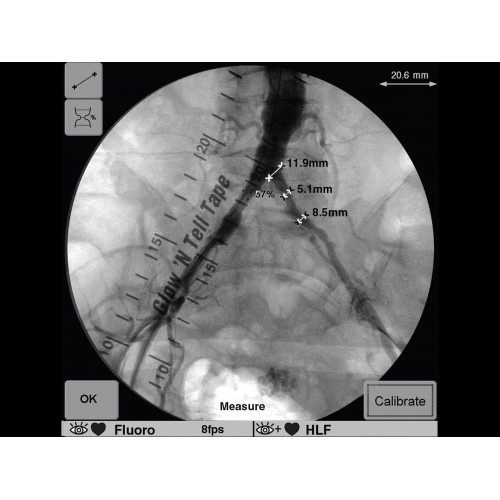

В ведущих медицинских центрах GE OEC 9900 Elite успешно применяется для проведения сложных кардиологических, нейрохирургических и ортопедических вмешательств. Система доказала свою эффективность при выполнении стентирования коронарных артерий, эмболизации сосудов головного мозга и вертебропластики. Многие учреждения отмечают повышение качества операций после внедрения этого оборудования.